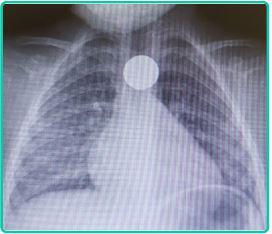

Júlio tem 2 anos e é levado pela mãe à emergência por choro, irritabilidade e desconforto cervical. Diante da radiografia de tórax mostrada a seguir, qual seria a sua conduta?

Trata-se de uma bateria impactada no esôfago, a conduta é a remoção imediata por endoscopia.

Trata-se de uma moeda impactada no esôfago e deve ser retirada endoscopicamente porque o paciente está sintomático.

Trata-se de um objeto arredondado e não traumático, podendo ser observado por 12 a 48 horas e removido apenas em caso de não migração.